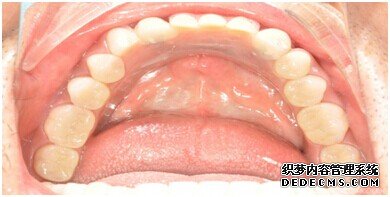

牙齿拍片初步检查

刘女士牙齿拍片初步检查

专家诊断:最后一颗牙齿通常不易清洁,且牙齿长了蛀牙之后也不容易发现,很多人就跟 刘女士一样发现的时候就已经是蛀牙中期甚至是后期了,这个时候一定要尽早治疗。不然和刘女士一样必须拔牙是非常可惜的。

由CT片检查来看,刘女士口腔健康环境还是很好的,牙槽骨也适合种植牙的条件,而且由我们最后一颗牙是非常重要的,经过专家的建议和详细解释了原因之后,刘女士选择了美国百康种植牙。